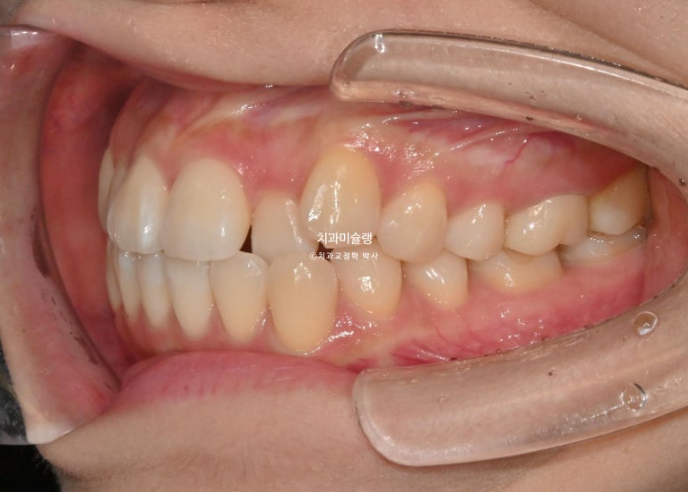

25년 9월부터 12월까지, 10개의 추가장치를 모두 낀 후 치료를 마무리 했습니다.

중심선은 완벽히 맞으며 앞니 배열과 높낮이는 교과서적입니다.

원래 좋았던 어금니 교합은 잘 유지되었습니다.

이제 전후비교 볼게요. 총 치료기간은 9개월입니다.